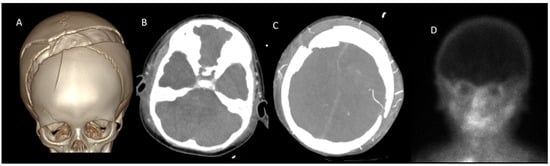

2.1. Study Population

| Open Fontanel | 12 (27.9) |

| Craniectomy | 2 (4.7) |

| Fracture | 5 (11.6) |

| Shunt | 5 (11.6) |